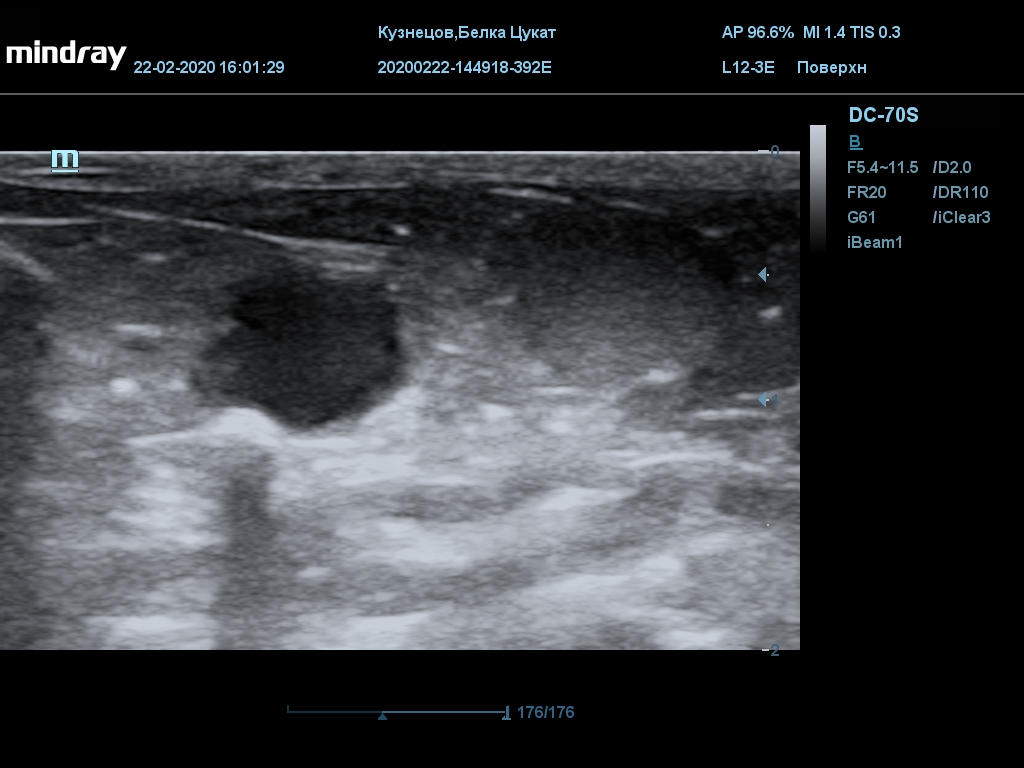

УЗИ

(почки, мочевой пузырь и, предположительно, простата)

Обращаю внимание, что делала УЗИ и писала заключение узист, которая специализируется на кошках и собаках, поэтому она сделала узи и описала, как смогла, но тонкостей грызунячьей анатомии она не знает.

Приложил только фото, есть ещё пара видео, но не знаю, как тут выложить, и надо ли.

Мочевой пузырь объём 12,1 х 7,6 х 11 мм. Стенка не утолщена, 0,5 мм, содержимое не однородное, до половины объёма гипоэхогенная мелкодисперсная взвесь. Макс. размер включений 0,8 мм. Теней нет.

Каудальнее мочевого пузыря визуализируется округлая структура размером 11,1 х 8,3 мм с ровными контурами гипоэхогенная однородная, с признаками васкуляризации.

Почка левая ровная, размер 12 х 7,6 х 8,2 мм. Контур ровный чёткий. КМД отсутствует, лоханка расширена незначительно, объёмных включений не выявлено.

Почка правая ровная, контур чёткий, размер 13,5 х 8,7 х 9,3 мм. Капсула визуализируется. КМД отсутствует, лоханка не расширена. Объёмные образования не выявлены.

Заключение: УЗпризнаки уролитиаза, объёмная структура каудальнее мочевого пузыря. Признаки расширения левой лоханки.

УЗИ

(почки, мочевой пузырь и, предположительно, простата)

Обращаю внимание, что делала УЗИ и писала заключение узист, которая специализируется на кошках и собаках, поэтому она сделала узи и описала, как смогла, но тонкостей грызунячьей анатомии она не знает.

Приложил только фото, есть ещё пара видео, но не знаю, как тут выложить, и надо ли.

Мочевой пузырь объём 12,1 х 7,6 х 11 мм. Стенка не утолщена, 0,5 мм, содержимое не однородное, до половины объёма гипоэхогенная мелкодисперсная взвесь. Макс. размер включений 0,8 мм. Теней нет.

Каудальнее мочевого пузыря визуализируется округлая структура размером 11,1 х 8,3 мм с ровными контурами гипоэхогенная однородная, с признаками васкуляризации.

Почка левая ровная, размер 12 х 7,6 х 8,2 мм. Контур ровный чёткий. КМД отсутствует, лоханка расширена незначительно, объёмных включений не выявлено.

Почка правая ровная, контур чёткий, размер 13,5 х 8,7 х 9,3 мм. Капсула визуализируется. КМД отсутствует, лоханка не расширена. Объёмные образования не выявлены.

Заключение: УЗпризнаки уролитиаза, объёмная структура каудальнее мочевого пузыря. Признаки расширения левой лоханки.